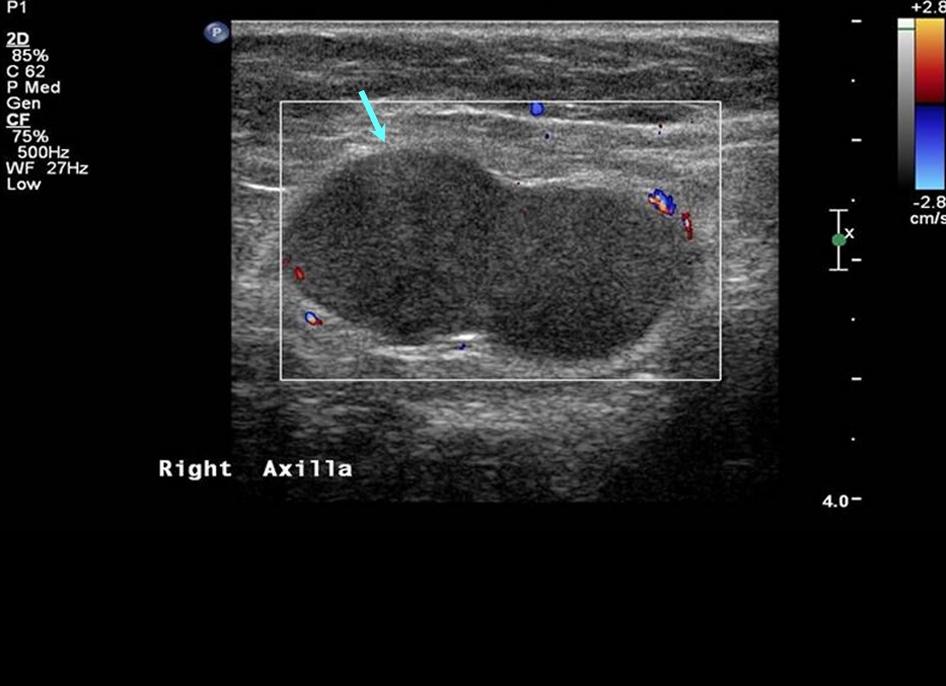

Инструментальная диагностика методом ультразвукового сканирования (УЗИ), которое также называется ультрасонографией, может выявлять во внутренних органах и полостях участки с различной акустической плотностью – гиперэхогенное или гипоэхогенное образование.

Локальное гипоэхогенное образование в том или ином органе, в отличие от гиперэхогенного, является результатом более низкой эхогенности тканей – в сравнении с параметрами акустической плотности здоровых тканей органа. То есть данный участок слабо отражает направленный на него ультразвуковой сигнал (в частотных диапазонах 2-5, 5-10 или 10-15 МГц). И это свидетельство того, что данное образование – с точки зрения его структуры – либо содержит жидкость, либо имеет полость.

Гипоэхогенное образование на экране визуализируются в виде серых, темно-серых и практически черных зон (при гиперэхогенности зоны светлые, часто – белые). Для расшифровки ультразвукового изображения существует шкала шести категорий серого Gray Scale Imaging, где каждый пиксель полученного на мониторе изображения гипоэхогенного образования – в зависимости от силы ультразвукового сигнала, возвращающегося на датчики – представляет собой конкретный оттенок серого.

Во многих случаях требуется дифференциальная диагностика, для чего, кроме УЗИ, используются другие аппаратные методы визуализации патологии (ангиография, цветная допплерография, КТ, МРТ и т.д.), а также проводится гистологическое исследование биоптатов.